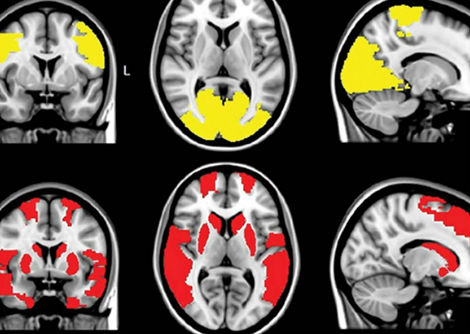

في عدد أبريل 2021 الصادر عن The Scientist ، يفترض العالم / المؤلف Paul Mischel من جامعة ستانفورد وجود توازن مثير للاهتمام بين التقدم العلمي في مجال علم الفلك وكيف يستكشف علماء الأحياء العالم الحي. يشرح ميشيل في قصته المميزة ، "السرطان قد يكون مدفوعًا بالحمض النووي خارج الكروموسومات" ، كيف يمكن للخرائط في كلا المجالين أن تقود اكتشاف الحقائق العلمية وتوصيفها عن مسارها أحيانًا. في حالة علم الفلك ، تضمنت الخرائط عرض بطليموس المتمحور حول الأرض للكون والخرائط المصححة التي تم إجراؤها بعد 1400 عام بواسطة القديس الراعي لعلم الفلك ، المفكر في عصر النهضة نيكولاس كوبرنيكوس. في حالة السرطان ، تفقد خرائط الجينوم عنصرًا رئيسيًا: الحمض النووي خارج الصبغيات (ecDNA). يشبّه ميشيل القفزة المفاهيمية المتمثلة في اعتماد نموذج محوره الشمس للنظام الشمسي بما هو مطلوب الآن في مفهوم العلم لديناميكيات السرطان.

وهذا هو الوعد الذي تحمله الرؤى مثل دور ecDNA. قد يؤدي دمج هذا المكون الجديد في النماذج الحالية لديناميكيات السرطان إلى طرق جديدة للتغلب على المرض ، في العديد من تعابيره المميتة. إن دمج ecDNA في الخرائط الجينية القديمة للسرطان ، والتي تركز على الحمض النووي الصبغي الأكثر قابلية للتتبع ، لا يقلب النموذج بأكمله. إنه فقط يعيد تركيزه بطريقة قد تؤدي فقط إلى تحويل مركز الثقل للعاملين الجزيئيين المخططين بدقة. مثل تلسكوب جاليليو ، تؤكد التقنيات الجينومية المتقدمة التأثير البيولوجي للـ ecDNA وتسمح للباحثين بالعثور على المزيد والمزيد من السياقات التي قد تؤدي فيها المكونات الجينية التي تم تقديرها حديثًا إلى حدوث المرض.